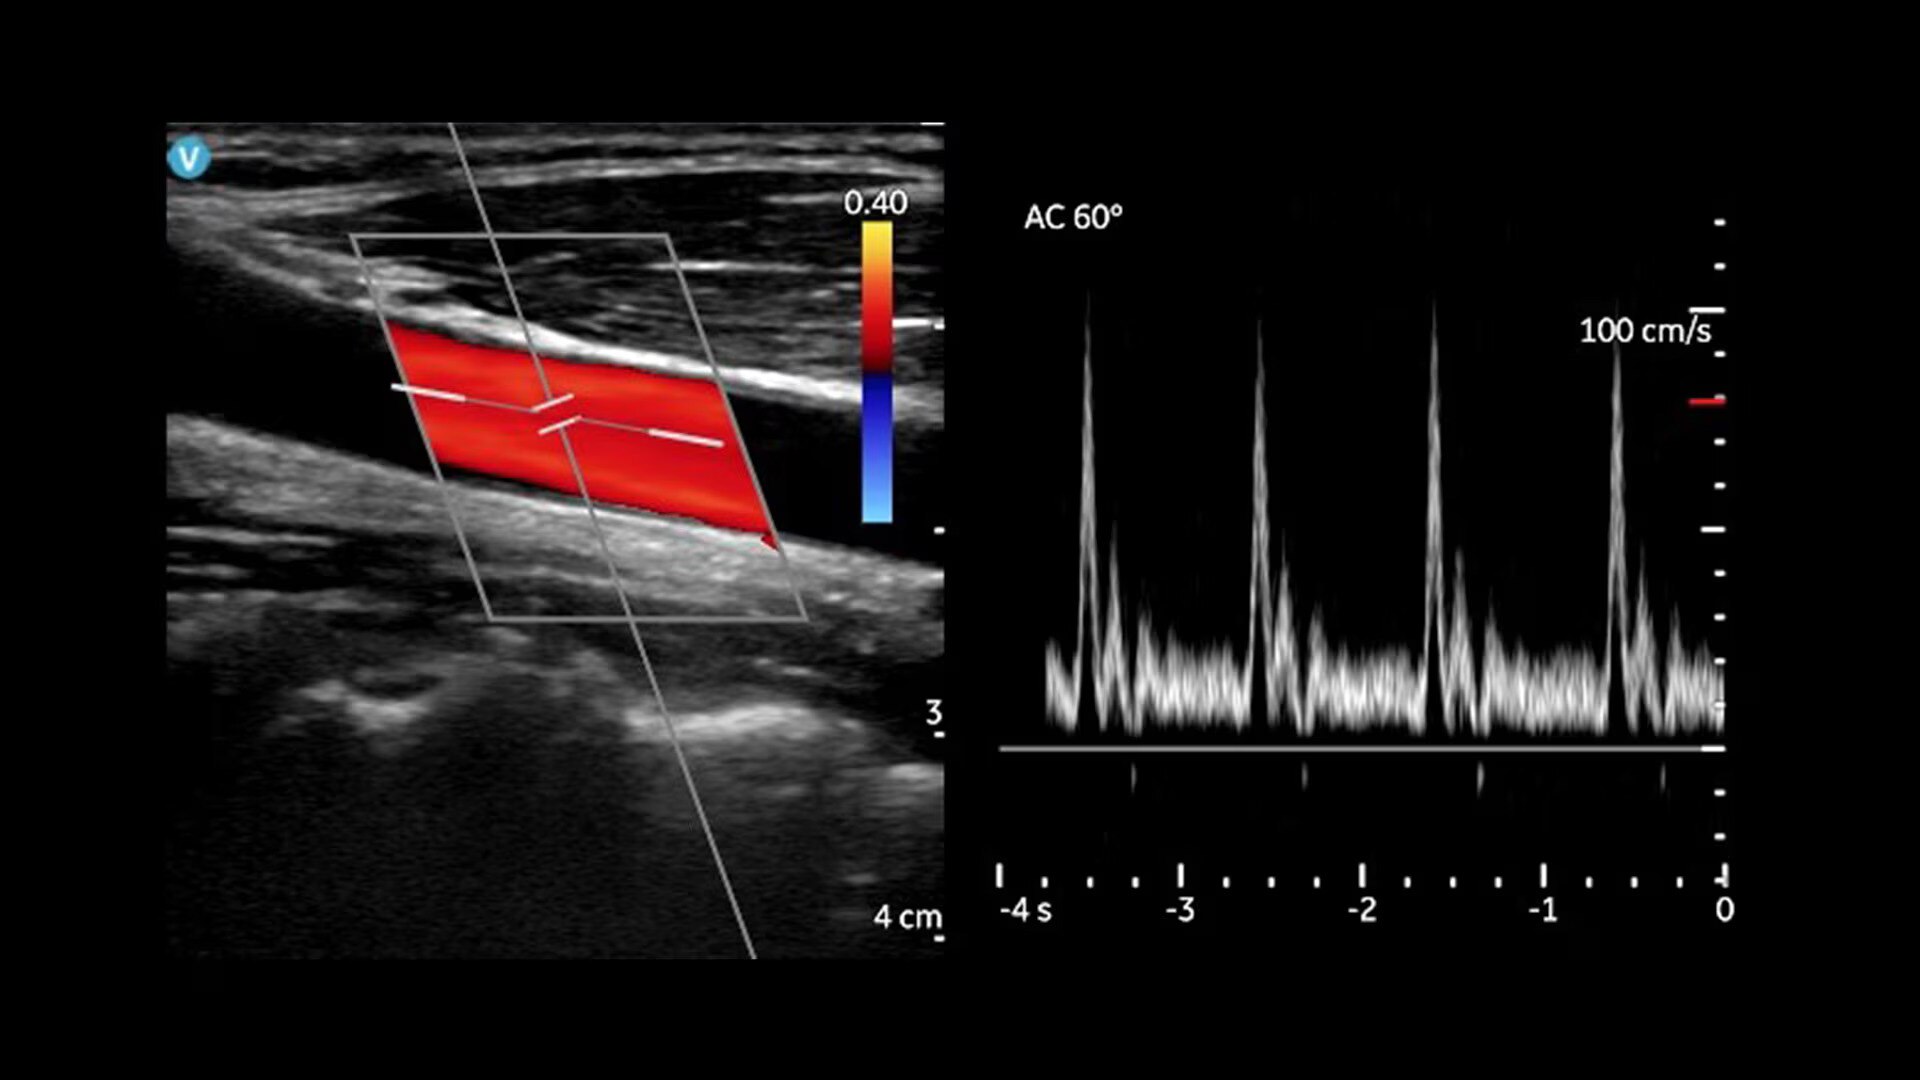

Key features for all users and specialties

Built for both new and experienced handheld ultrasound users with basic and advanced assessments in mind. Now including: B-mode; Color Doppler; PW Doppler; M-mode; and OB measurements.